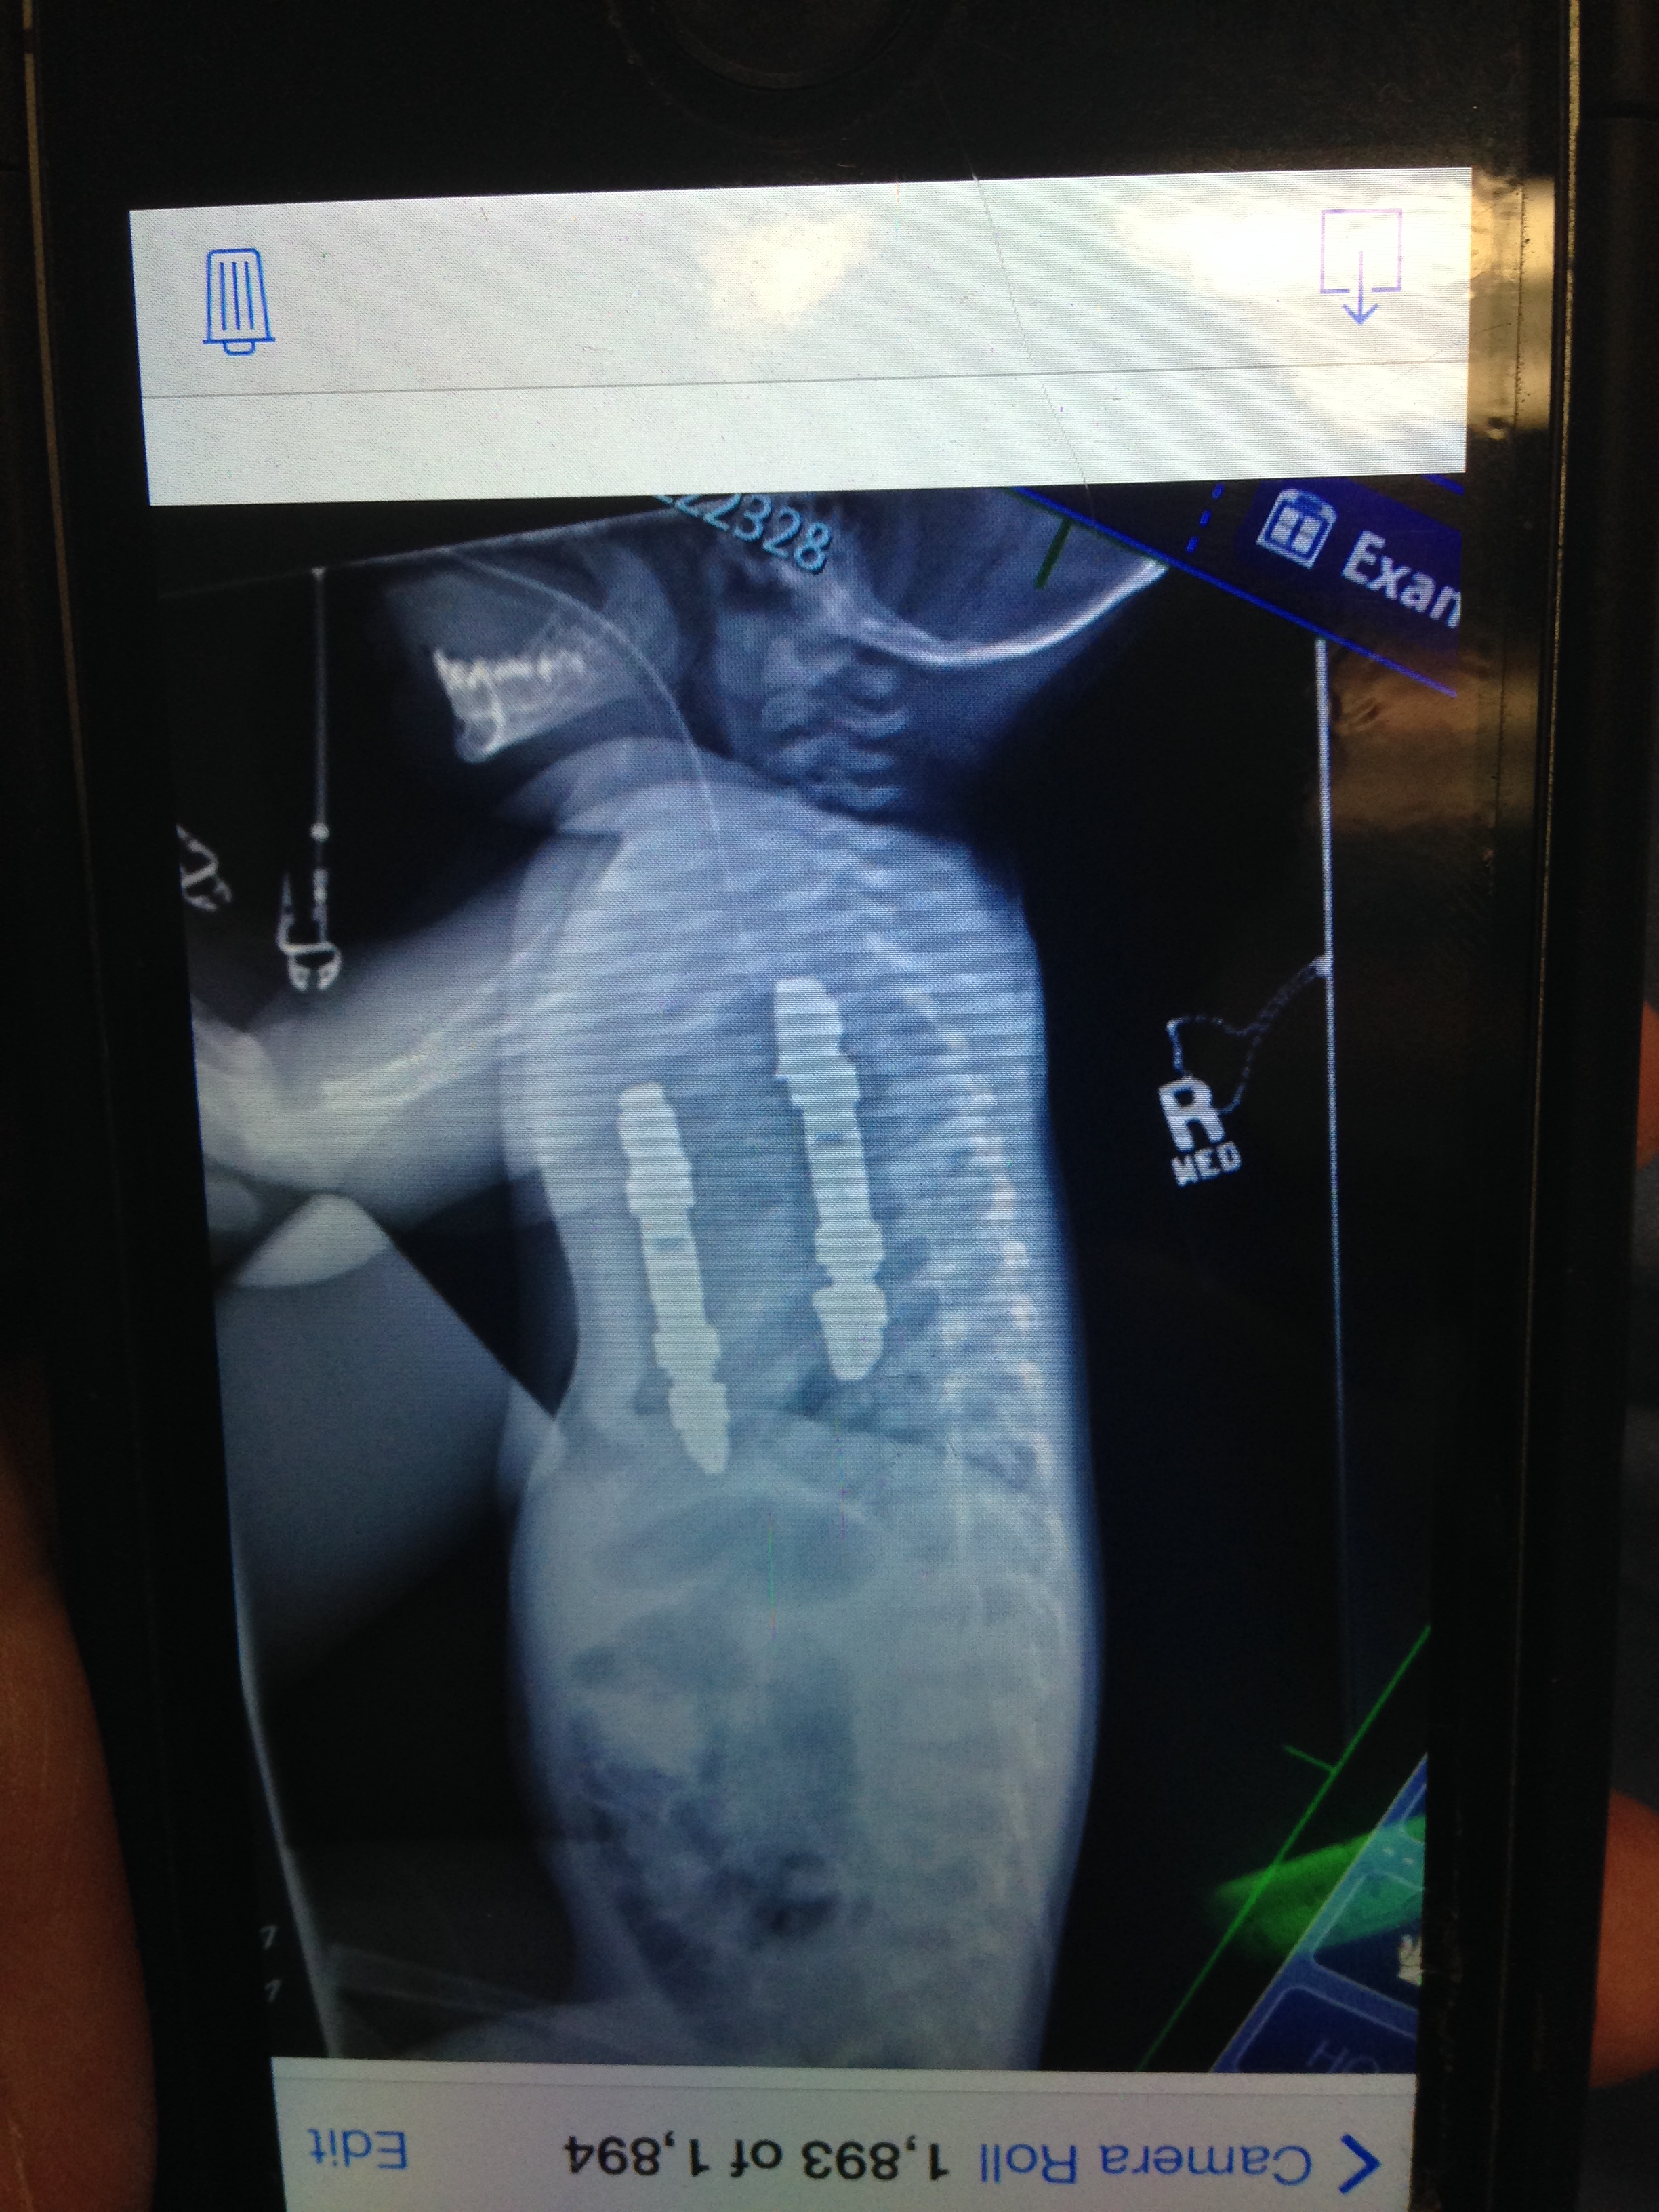

In January of 2013 Michael’s curve increased to 63* and 53” and it was decided it was time to consider surgery. He repeated MRI’s to make sure there were no changes to his spinal cord. He was scheduled for surgery in April but due to some issues with lab work at the very last minute it was continued to May of 2013. His surgeon did a great job of explaining the surgery in detail. It was very hard to hear that the plan was not to “straighten” his spine, but to stop the progression from going any further. He explained that attempting to straighten his spine completely could compromise his spinal cord and was too risky. The thought of going through such a big surgery without the benefit of looking better afterwards was pretty devastating for Michael to hear. The surgeon decided to not fuse the bottom compensating curve to leave him with more flexibility and the hope that it would compensate back. Michael had a pic line put in the day before surgery as an outpatient procedure.

His surgery was supposed to start at 7am the next morning, but was delayed until about 9am. It was a stressful morning for Michael. It was stressful once they started the surgery because we did not receive any updates until the surgery was done at about 7pm. It then took another hour and a half to close him up. The doctor ended up completing a posterior spine arthrodesis and fusing from T1 to L2. He said he was a little nervous halfway through the surgery because he was so small and thin but it all worked out when it was time to close him up. I was not able to actually see him in recovery until about 10pm. The doctor had prepared me for his face to be swollen but I don’t think anything could have actually prepared me for what he was going to look like. It almost looked like someone else’s child. When they are on their stomachs for so many hours it’s natural for that to happen. It took a few days for the swelling to go down.

Michael had his first post x-ray at about 6 weeks after surgery. It was amazing to see the difference. He actually gained 2 inches in height when he came home from surgery. This x-ray was the first time we could see his 2 rods and 20 screws. Even though the plan wasn’t to straighten his spine, his back looked great. The compensating curve did not compensate back as hoped so he has a 38* curve on his hip that has stayed consistent.